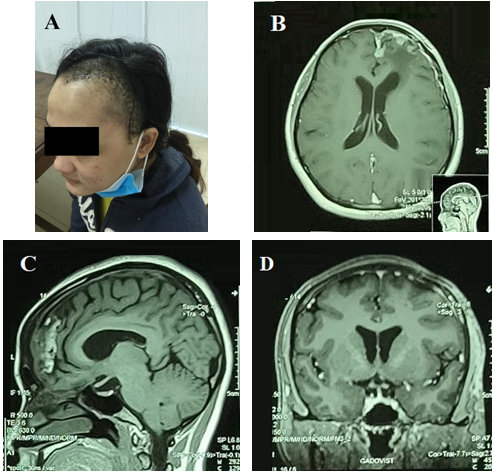

Hai tháng sau phẫu thuật, bệnh nhân được chuyển đến khoa ngoại thần kinh để đánh giá và kiểm tra tâm lý thần kinh. Các triệu chứng của bệnh nhân đã được giải quyết sau khi phẫu thuật và chất lượng cuộc sống của bệnh nhân cũng được cải thiện đáng kể.

Hình 3. Hình 3A. Bệnh nhân tái khám sau mổ 2 tháng. Hình 3B-3C-3D (mặt phẳng cắt ngang, cắt dọc đứng, cắt dọc ngang) Cộng hưởng từ sau mổ ghi nhận khối u màng não thùy trán trái đã được lấy bỏ hoàn toàn.